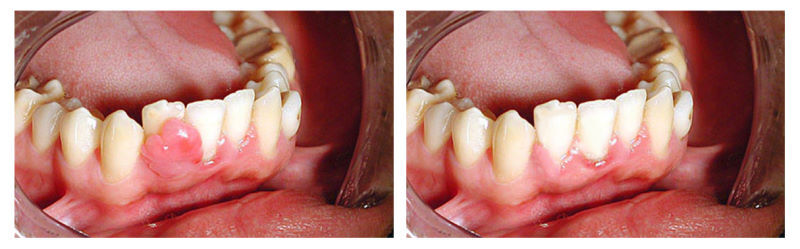

Киста зуба под коронкой: фото до и после